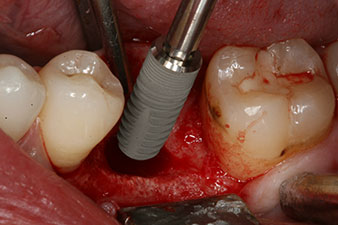

Implantat

Fig. 3: After preparation with the Implantmed implantology motor, an implant (diameter 4 mm, length 12 mm) was screwed in by the motor at a torque of 43 Ncm.

The implant was placed as planned after thorough removal of the granulation tissue (blueSky, bredent).